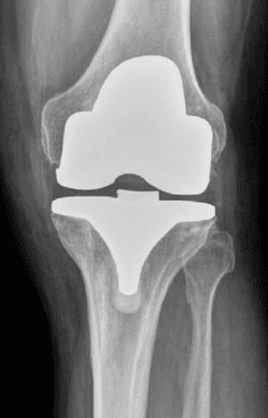

Hemarthrosis can be a postoperative complication of arthroscopic surgery, for example, following total knee replacement. Roughly 0.3% of patients who undergo total knee replacement develop recurrent hemarthrosis. The bleeding occurs, on average, around 2 years after the operation. This occurs due to very vascular synovial tissue within the joint that bleeds due to repetitive trauma. Typically, patients require 3-4 joint aspirations (drainage of the blood from the joint). However, some patients do not respond to conservative treatments or have severe bleeding. Such patients require a more definitive treatment such as hemarthrosis embolization.

Recurrent hemarthrosis can also be treated by aspiration, surgical removal of the synovial tissue or embolization. Hemarthrosis embolization can be considered as a minimally invasive solution for patients with recurrent hemarthrosis who have failed to respond to conservative treatment and/or repeated joint aspirations. Angiography allows for visualization of the abnormal vessels (geniculate arteries) in the joint and treatment can be performed at the same time. Open surgical removal of the joint tissue (synovium) is also reported to be successful but in the setting of repeat surgery has higher rate of complication and morbidity, such as loss of function and infection.

Embolization is a procedure in which the blood supply to a specific area is blocked. Hemarthrosishemarthrosis geniculate artery embolization treatment specialist embolization addresses the root cause of the problem, i.e., it blocks the abnormal arteries causing the bleeding into the knee joint.

Oftentimes, the culprits are the geniculate arteries that extend out into the knee joint and cause intermittent bleeding. Embolization of the geniculate arteries is a safe and effective treatment for recurrent spontaneous hemarthrosis after total knee replacement.

When someone has recurrent hemarthrosis after total knee replacement (bleeding continues to occur despite three or more joint aspirations), embolization offers a definitive solution. The exact source of bleeding is confirmed with angiography (imaging) and the bleeding artery is blocked with embolization. Compared with open surgery, embolization can be performed under local anesthesia, lowers the risk of infection, and expedites postoperative recovery.